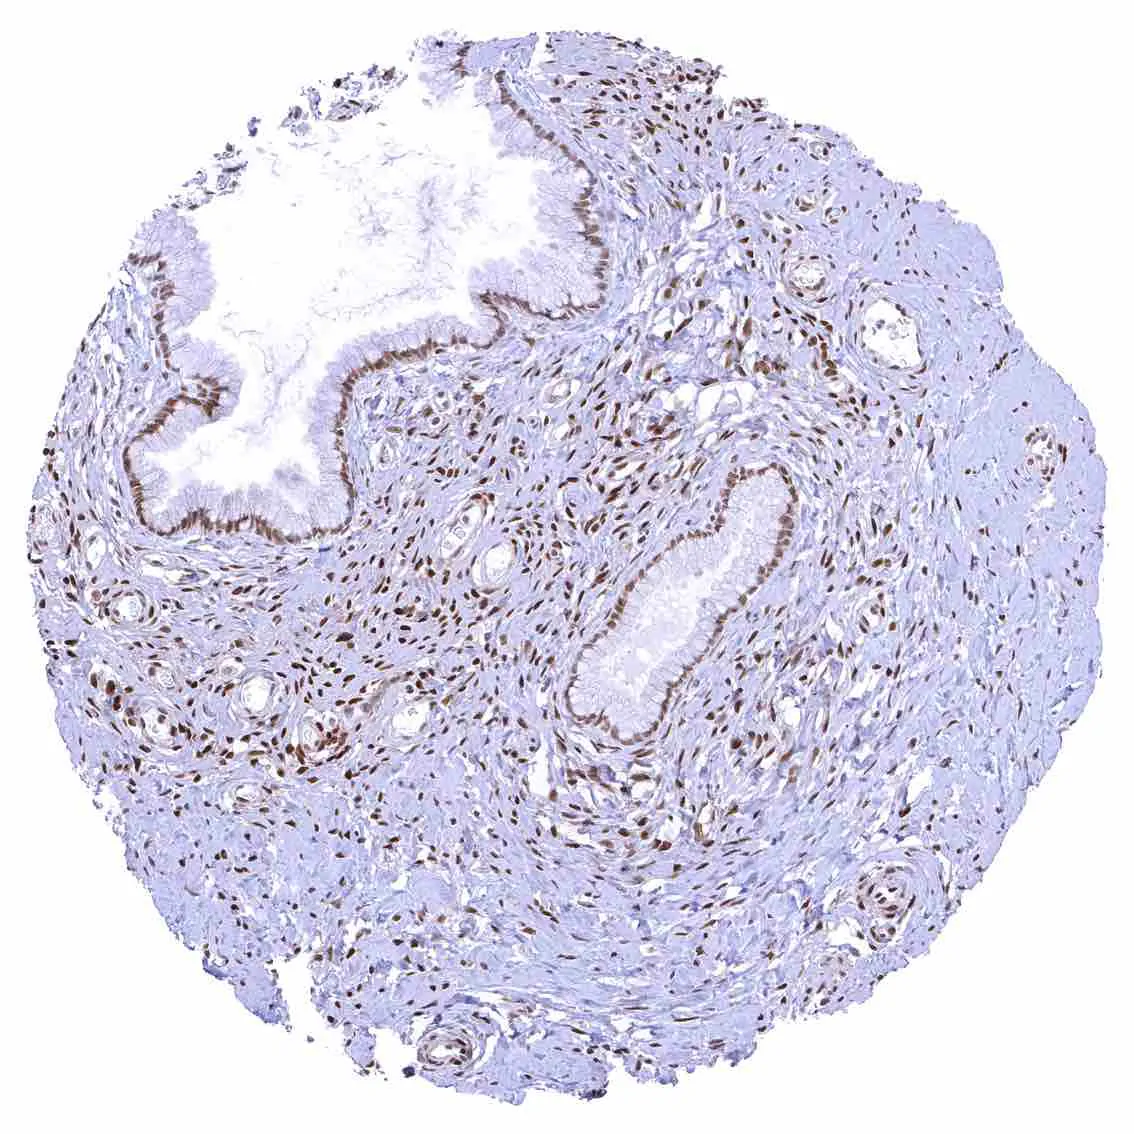

Uterus, ectocervix – Nuclear staining of squamous epithelial cells predominates in the more mature cell layers (top 50_ of the epidermis).